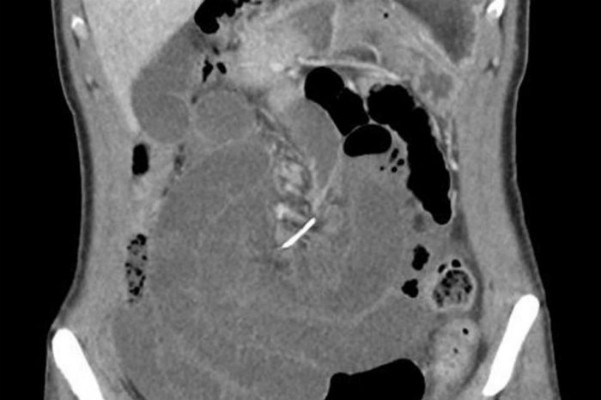

Một phụ nữ 30 tuổi ở Australia nhập viện trong tình trạng đau bụng dữ dội vì có một đoạn kim loại dài 7 cm đâm thủng ruột non. Ruột non của người này bị xoắn xung quanh. Bác sĩ phẫu thuật cấp cứu để lấy dị vật ra, phát hiện đó là sợi dây kim loại của chiếc niềng răng.

Người phụ nữ cho biết đã đeo niềng răng từ 10 năm trước và không nhớ nuốt phải sợi dây này lúc nào.

| Mảnh kim loại của chiếc niềng răng đâm thủng ruột non người phụ nữ. |